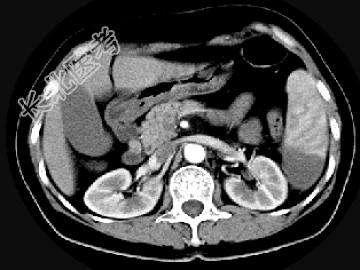

- 单项选择题女,54岁, 左上腹痛,CT检查如图, 最可能的诊断是 ( )

A、脾淋巴瘤

B、脾脓肿

C、脾梗死

D、脾血管瘤

E、脾转移癌